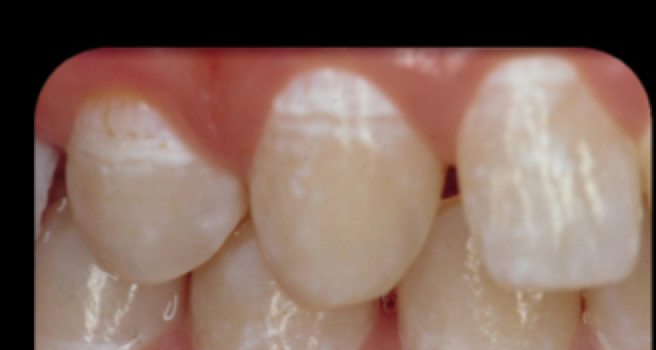

1-first visual change in enamel

2-distinct visual change in enamel

3-localized enamel breakdown bc of caries w/ no visible dentin

4-non cavitated surface w/ underlying dark shadow from dentin

Active Lesion

Inactive Lesions

Inactive White Spot Lesion—–reversible & stable

Decalcification

Fluorosis